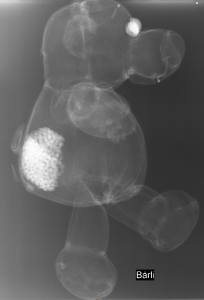

Erst das Kuscheltier - dann das Kind

Galerie der Kuscheltiere

Kinder kommen oft sehr ängstlich mit Kuscheltieren oder Puppen zum Röntgen. Um den Kindern diese Angst zu nehmen, kann man vor deren neugierigen Augen, zuerst die kuscheligen Begleiter unter die Röhre legen.

Spätestens wenn die Kinder die Bilder Ihrer Kuscheltiere sehen ist die Angst vorm Röntgen meist vergessen. So wie bei den unten abgebildeten Bildern.

Galerie wird ständig erweitert!